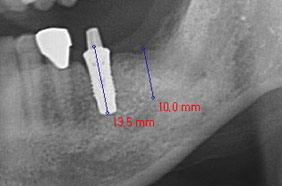

植牙後的2D影像看似正常

3D影像發現植體穿出骨頭外

平切面

縱切面